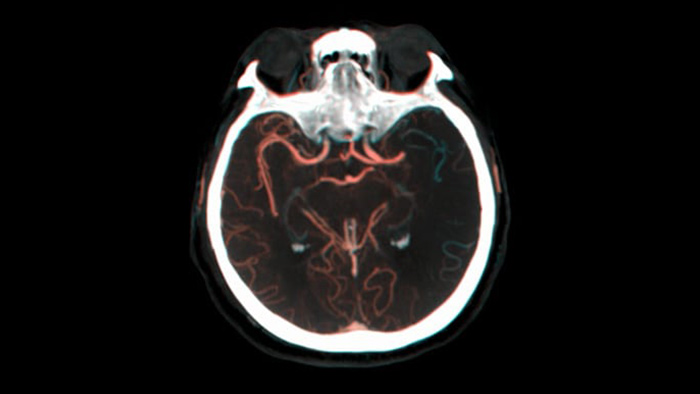

Ver llenado colateral

Visualización del llenado colateral

La vista dual para ver los volúmenes de TC de haz cónico de fase temprana y tardía uno al lado del otro mejora la identificación de las áreas de penumbra y permite la visualización del relleno colateral.

Control periprocedimiento de hemorragias

SmartCT soft tissue

Use las imágenes de SmartCT Soft Tissue (similar a una TC) de la suite Neurovascular para comprobar el éxito del tratamiento e identificar hemorragias.

Imágenes nítidas con DSA 2D con tecnología ClarityIQ

Angiografía por sustracción digital (ASD) 2D con tecnología ClarityIQ

ClarityIQ aplica la compensación automática del movimiento durante la DSA en tiempo real para mantener imágenes nítidas de los vasos. Esto permite tomar decisiones con confianza durante los procedimientos para atender accidentes cerebrovasculares.

Confirmar el éxito del tratamiento

Visualización de la ASD

Las visualizaciones de la DSA de alta calidad le permiten evaluar si ha recuperado el coágulo completo y si los trozos de coágulo se han dispersado distalmente en el cerebro. Puede comprobar el restablecimiento del flujo sanguíneo en las áreas de penumbra y comprobar si hay hemorragias periprocedimiento.